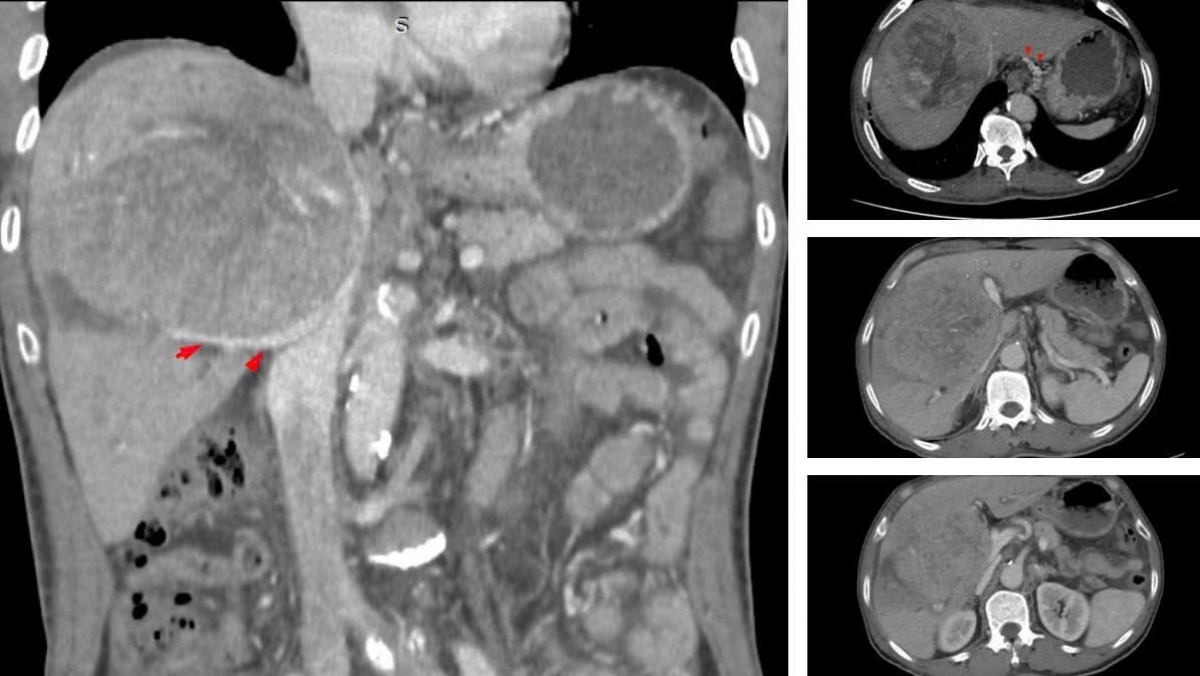

Trước tháng 7/2023, dù cơ thể đã có những phản ứng bất thường, nhưng ông N.V.T chủ quan không đi khám. Kết quả khi kiểm tra khối u gan đã đạt kích thước khổng lồ 10–12 cm, chiếm gần hết nhu mô gan, chèn ép rốn gan và tĩnh mạch, gây ra tình trạng cổ chướng nhẹ và phù hai chân. Tại một số cơ sở y tế, ông từng được tiên lượng thời gian sống có thể không quá 9 tháng.

Theo BSCKII Nguyễn Trường Giang, Phó Giám đốc Trung tâm Phẫu thuật Gan mật - Tiêu hóa, đây là một ca bệnh rất nặng. Các bác sĩ đã quyết định tiến hành cuộc đại phẫu cắt gan trung tâm kéo dài gần 8 giờ. Tuy nhiên, sau mổ, bệnh nhân xuất hiện biến chứng rò mật và hẹp tắc đường mật phân thùy sau. Tình trạng nhiễm trùng đường mật diễn biến nặng với vi khuẩn đa kháng thuốc kèm theo suy gan, khiến quá trình điều trị kéo dài với diễn biến vô cùng phức tạp.

Đến tháng 12/2023, khi thể trạng ổn định, các bác sĩ quyết định phẫu thuật lần hai để xử lý triệt để nguồn rò mật và ổ nhiễm trùng. Trong quá trình điều trị, bệnh nhân tiếp tục phát hiện thêm hai khối u tái phát – một đặc điểm thường gặp của ung thư giai đoạn muộn. Bằng sự phối hợp đa chuyên khoa giữa phẫu thuật, nút mạch và đốt u cao tần, các tổn thương dần được kiểm soát.